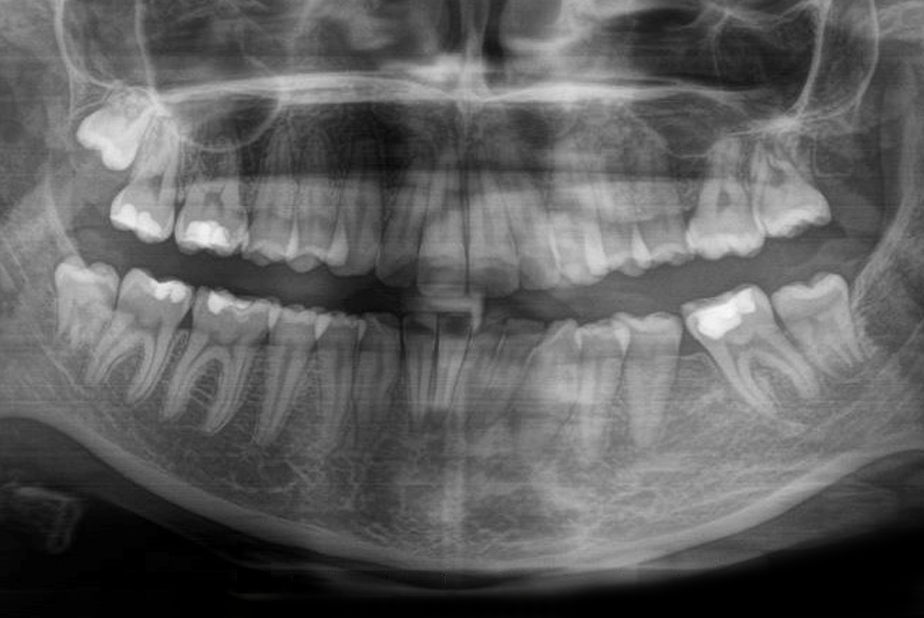

Ortopanoramica pre-trattamento della paziente. I due primi molari sinistri appaiono irrimediabilmente compromessi da carie destruenti

Fig. 1 Ortopanoramica pre-trattamento della paziente. I due primi molari sinistri appaiono irrimediabilmente compromessi da carie destruenti